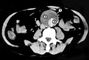

Эхография (см. Ультразвуковая диагностика) и компьютерная томография позволяют установить как наличие аневризмы аорты , так и ее протяженность, наличие в ней тромбов (рис. 3), отслоение интимы и образование гематомы при расслаивающей аневризме.